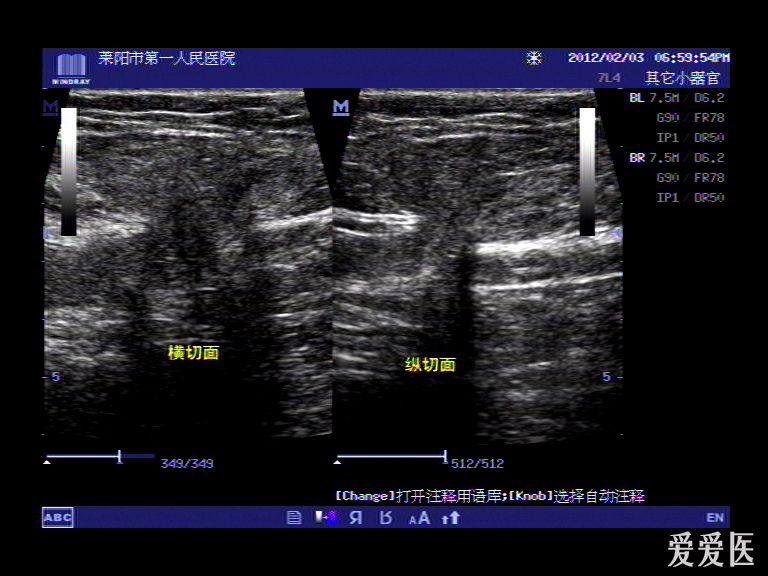

腹壁疝体表超声图

典型腹壁疝声像图